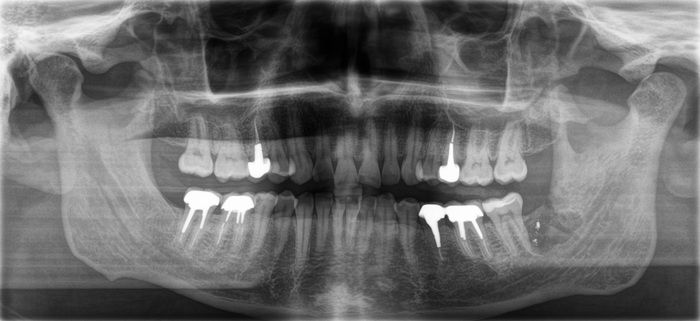

Контрольный рентгеновский снимок:

Вот так было:

А как стало на промежуточном этапе:

Согласитесь, выглядит очень даже неплохо, если опустить цвет.